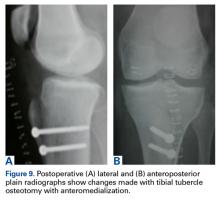

Lateralization or anterolateralization may be pertinent to revision if an osteotomy direction results in overcorrection of tuberosity position. Anteriorization ( Figures 2A-2C ) does not have a role in patellofemoral instability, but can unload areas of excessive patellar chondral force concentration at the central or proximal patella by increasing the angle between the patellar and quadriceps tendons and thereby decreasing the joint reaction forces. Straight medialization ( Figures 3A, 3B ) offloads lateral patellar chondral injury and may decrease lateral instability. Distalization ( Figures 4A-4C ) can correct for patella alta in the setting of patellar instability and allows earlier engagement of the patella in the trochlea to increase osseous restraint to lateral translation. 6Anteromedialization ( Figure 5 ) is indicated in patients with a normal proximal and medial patellar chondral surface and a laterally positioned patella leading to alteration of the contact area in the trochlear groove and resulting pain, lateral patellar or trochlear chondral disease, or instability. Osteotomy angle can provide varied medialization through consistent slope and anteriorization. For example, a 60° slope osteotomy provides 9 mm of medialization with 15 mm of anteriorization. 6 The procedure, similar to the additional TTO operations, begins with a lateral parapatellar incision that is extended distal to the tibial tubercle and anterior over the crest. The soft tissues around the tubercle are released to allow mobilization. Variable osteotomy jigs allow for different slope cuts for more medialization or anteriorization, based on preoperative findings. The osteotomy cuts are started with a thin oscillating blade ( Figure 6 ) and finished with an osteotome. The tubercle fragment ( Figure 7 ) is shifted and provisionally fixed with a Kirschner wire before being drilled and fixated with two 4.5-mm countersunk cortical screws ( Figures 8, 9A-9B ). Locally harvested corticocancellous bone can help anteriorize the tubercle block. Osteotomy specifics allow for corresponding anatomical translations of the TTO to address the preoperative pathology.Methods